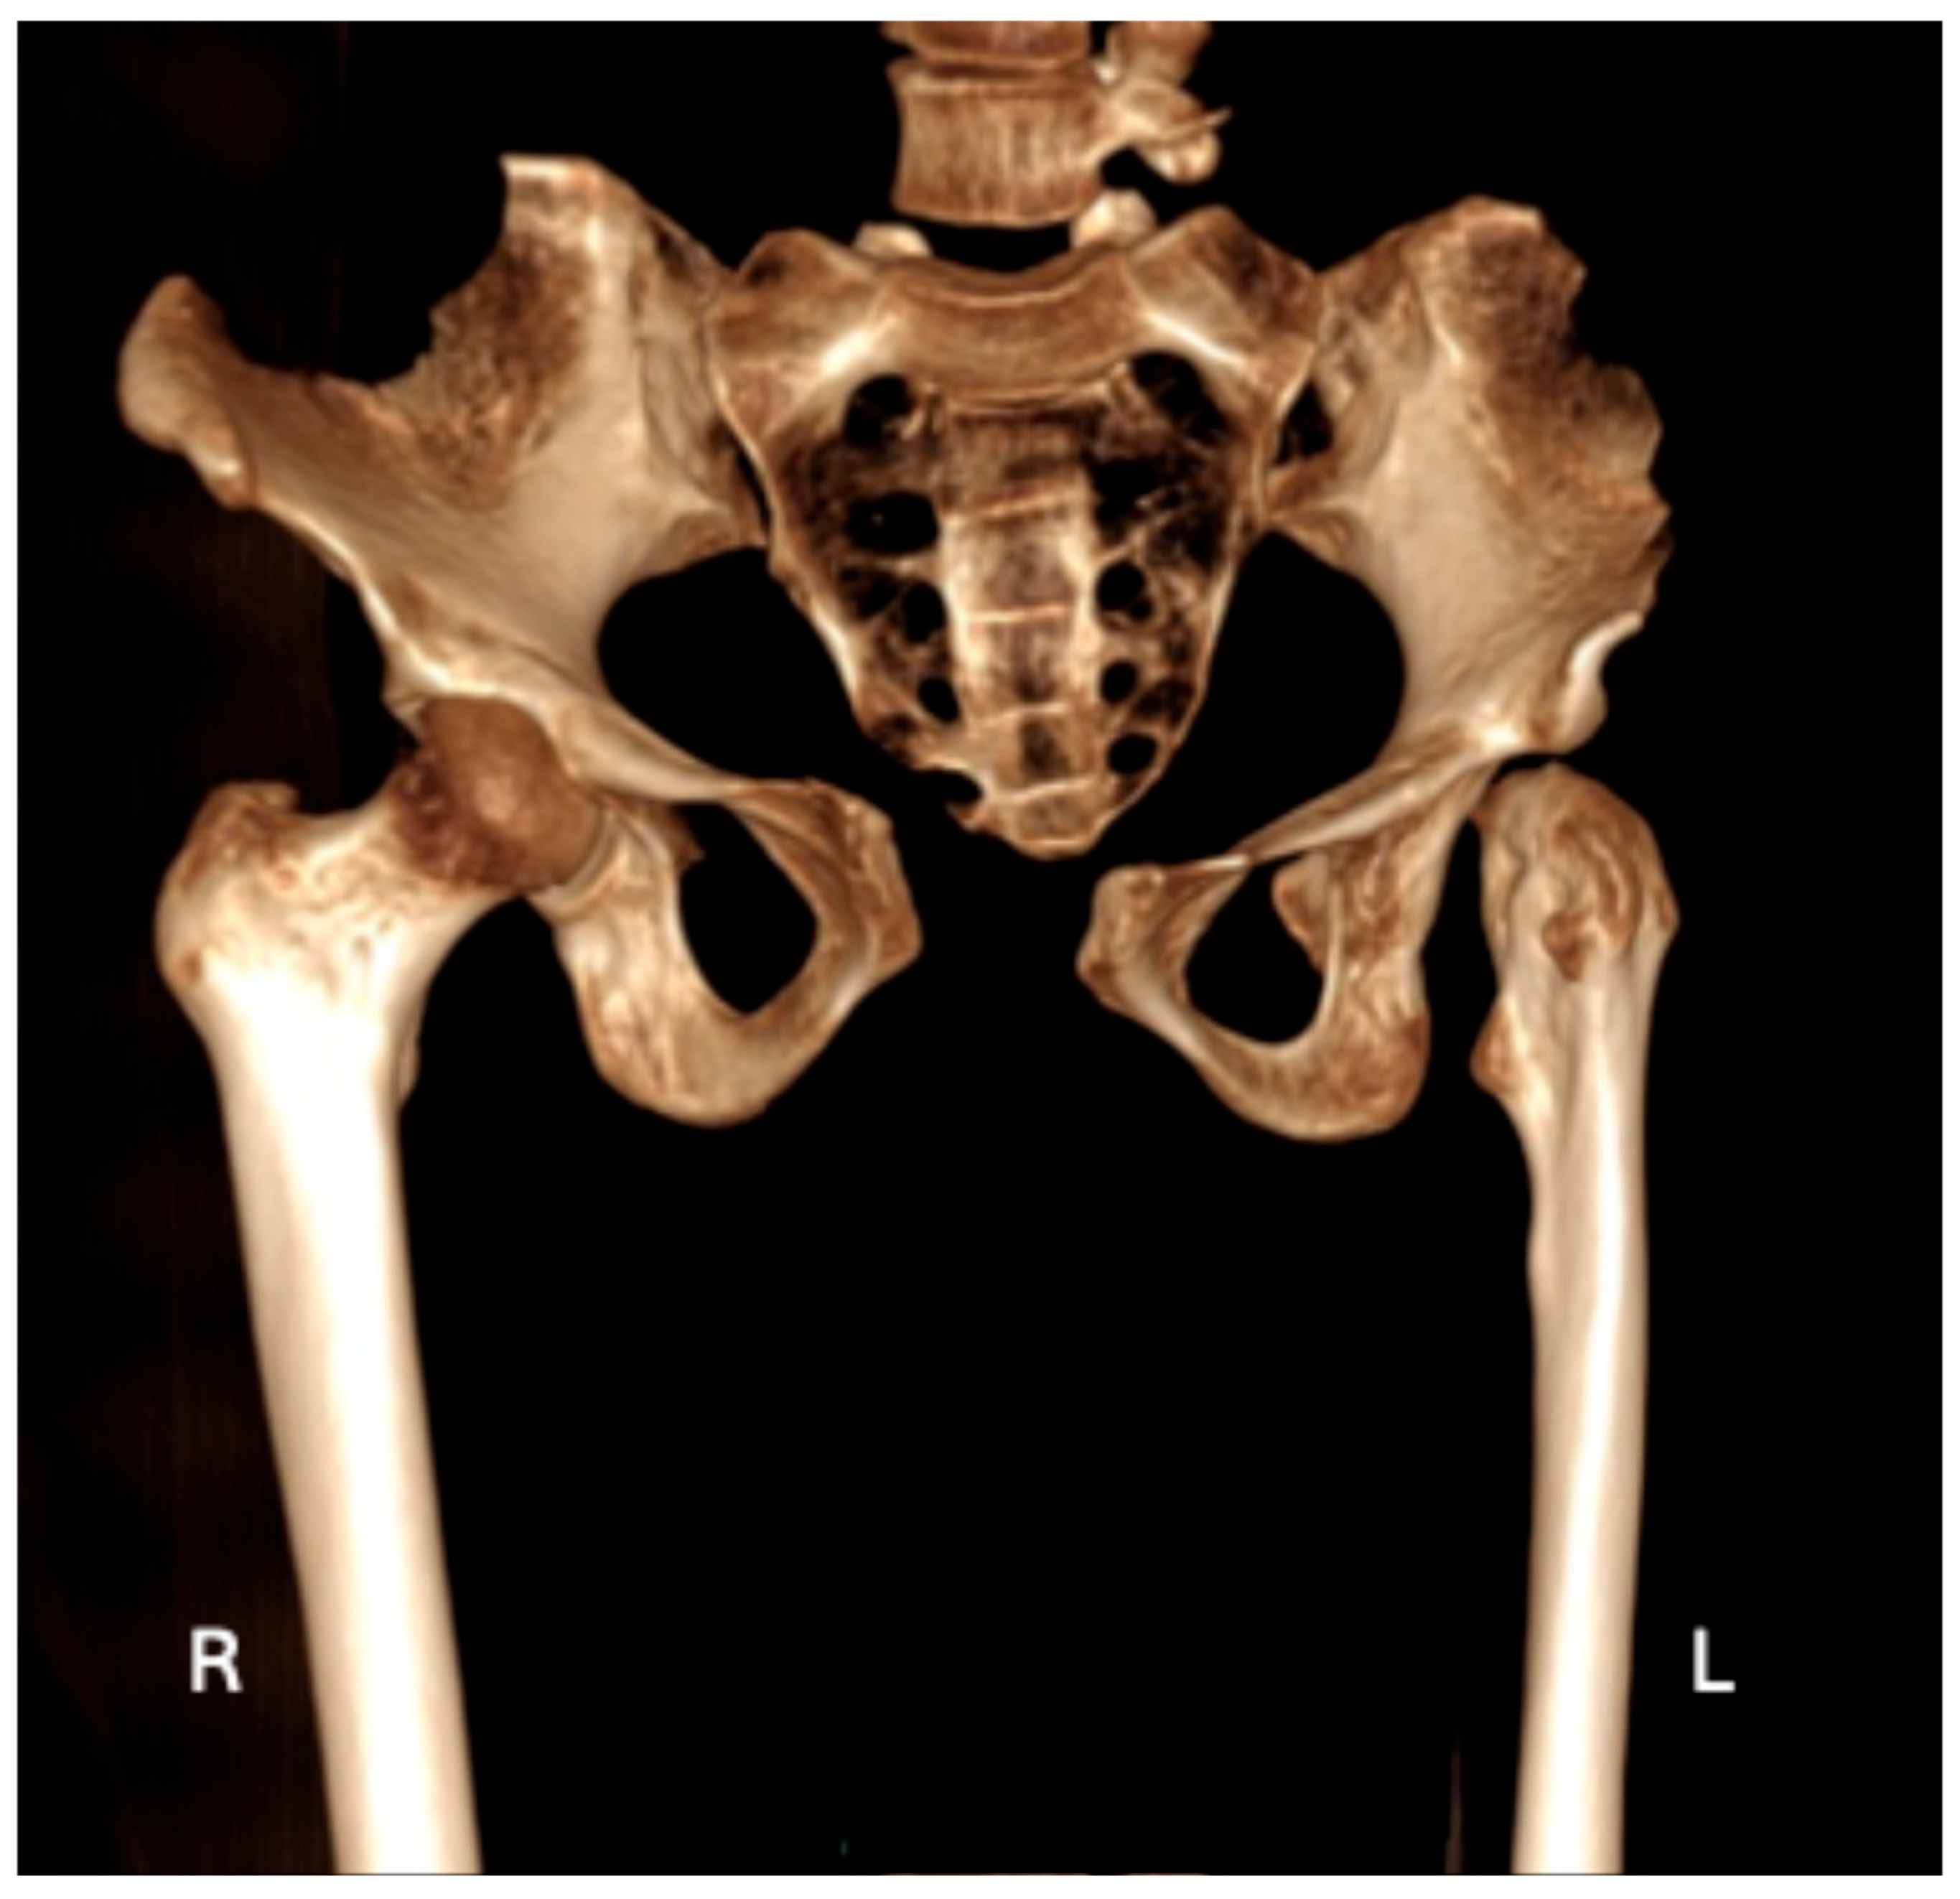

| Contralateral hip joint is definitively unaffected (Figure 4 and Figure 5) | X | X |

| Lack of development of the intertrochanteric crest (Figure 2a and Figure 4) | X | X |

| Lack of development of the trochanteric fossa (Figure 2a and Figure 4) | X | X |